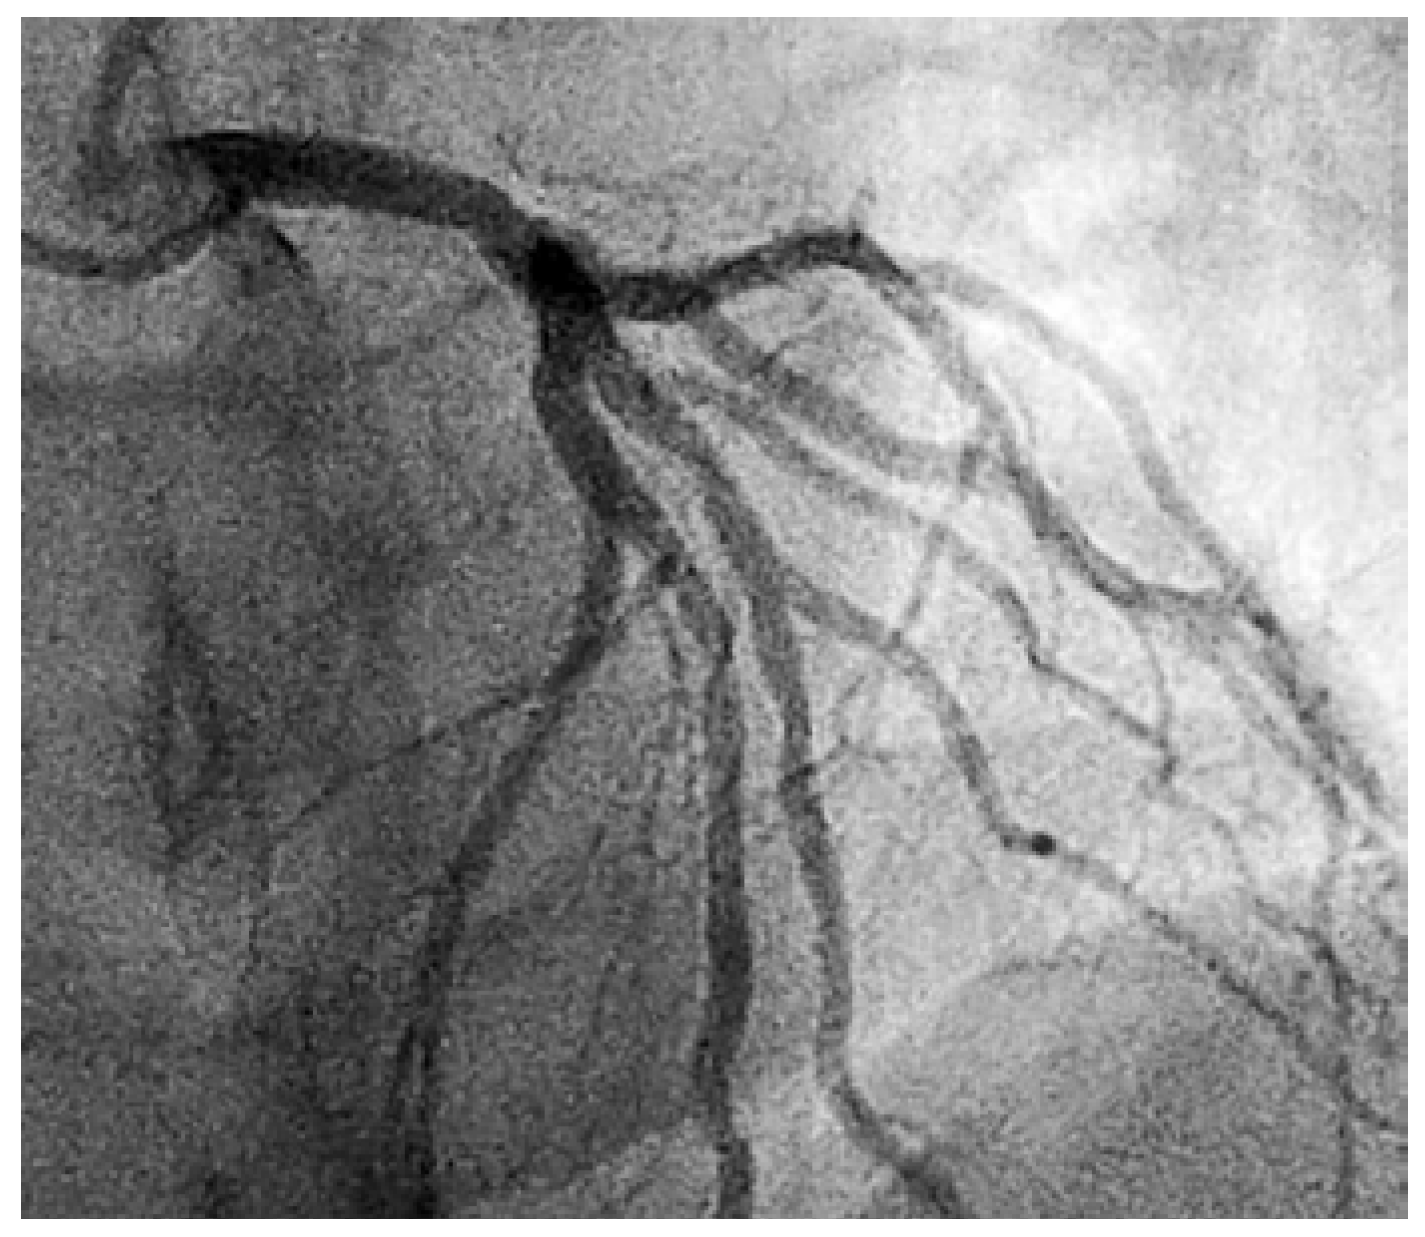

Als letzter meldete sich ein 44-jähriger Patient, bei dem eine Herzkatheteruntersuchung wegen familiärer Belastung durch ischämische Herzerkrankungen durchgeführt worden war (Befund auf der beiliegenden Abb. 1 ersichtlich). Im schriftlichen Bericht wurden eine 20–30% Hauptstammstenose und weitere nicht signifikante Verengungen beschrieben. Kurz vor Entlassung erhielt der Patient den Besuch einer Assistenzärztin, die ihm laut Aussagen des Patienten ziemlich unverblümt mitteilte: «Wenn dort etwas passiert, sind Sie tot». Im Übrigen müsse er dies mit dem Hausarzt besprechen. Sie hätte gerade keine Zeit für ein Gespräch.

Figure 1. Koronarangiographie.

Der Patient hätte sehr gerne mit dem untersuchenden Kardiologen die Befunde und deren Konsequenzen besprochen, aber letzterer war nicht mehr abkömmlich. Wie einfach wäre es gewesen, den Patienten zu beruhigen und ihm die nächsten Schritte verständlich zu erklären! Ich sah auf den vom Patienten per SMS zur Verfügung gestellten Abbildungen keine kritische Koronarverengung, beruhigte ihn telefonisch und empfahl ihm, die verschriebenen Medikamente einzunehmen.